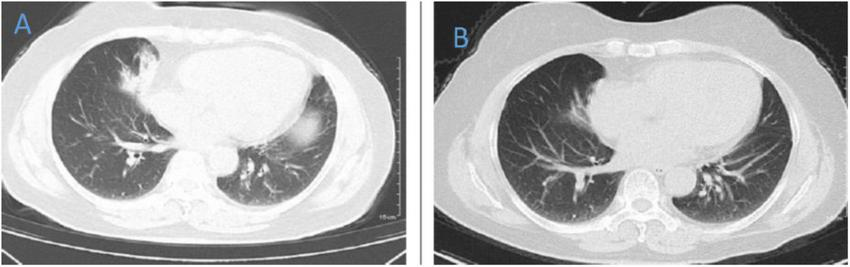

FIGURE 7

Chest CT of patient 7. (A) Before treatment on 2021.4.19. (B) The follow-up imaging 1 week after treatment showed progression compared to the pre-treatment scans.

FIGURE 8

Chest CT of patient 8. (A) Before treatment on 2022.1.10. (B) The follow-up imaging 1 week after treatment showed improvement compared to the pre-treatment scans.